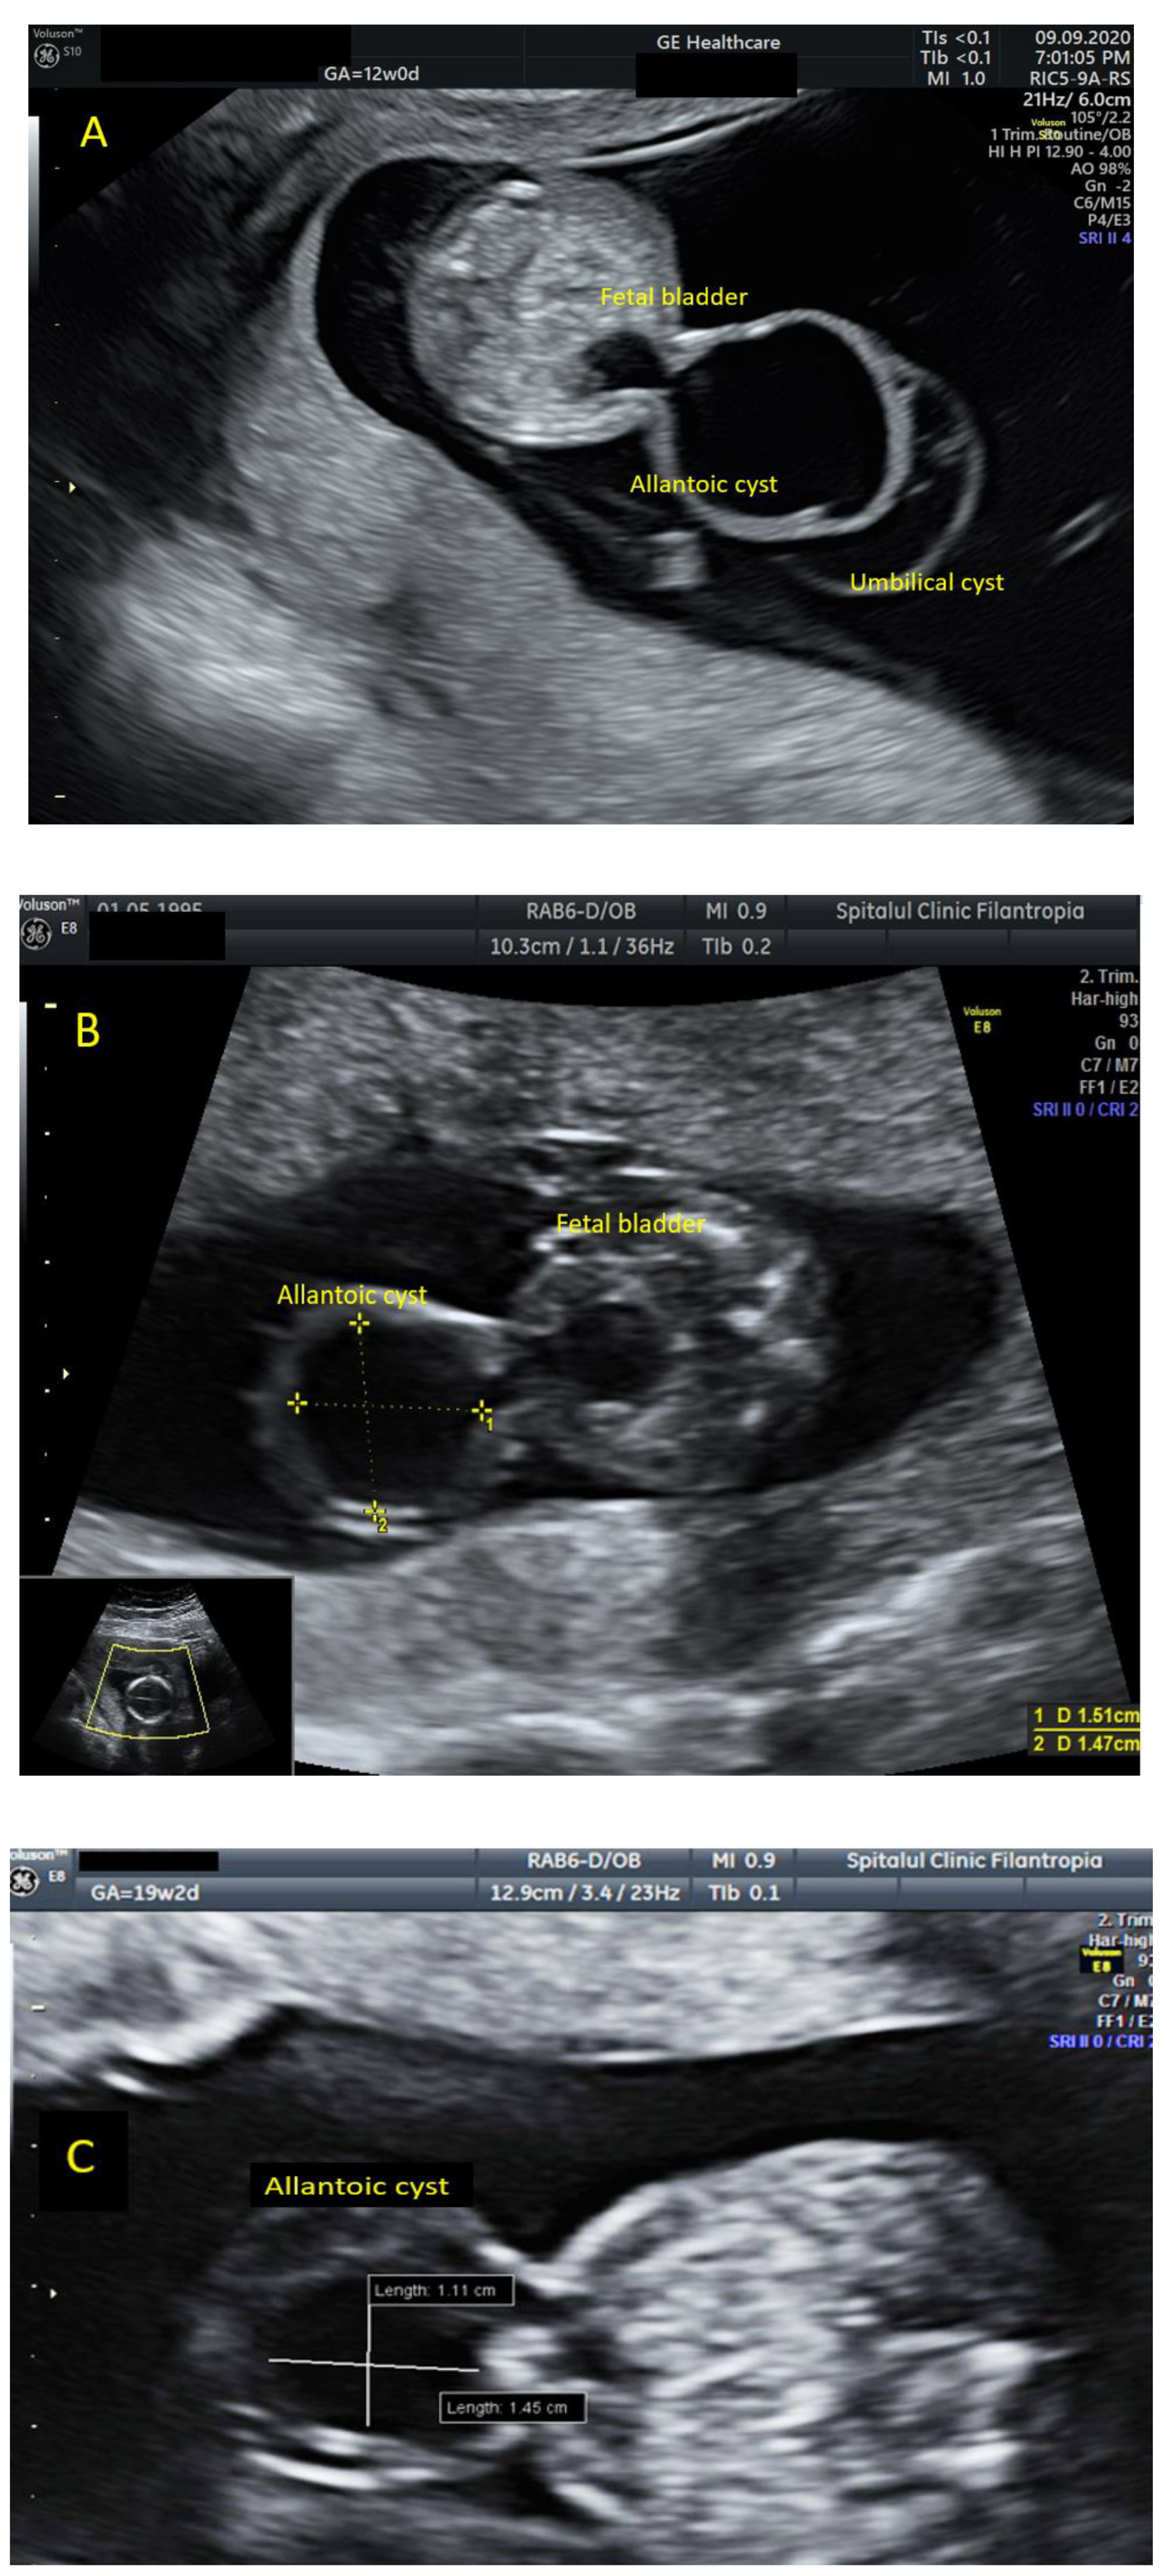

A Rare Case of Allantoic Cyst with Patent Urachus in Fetus with a Microdeletion in 1q21.1q21.2 Region